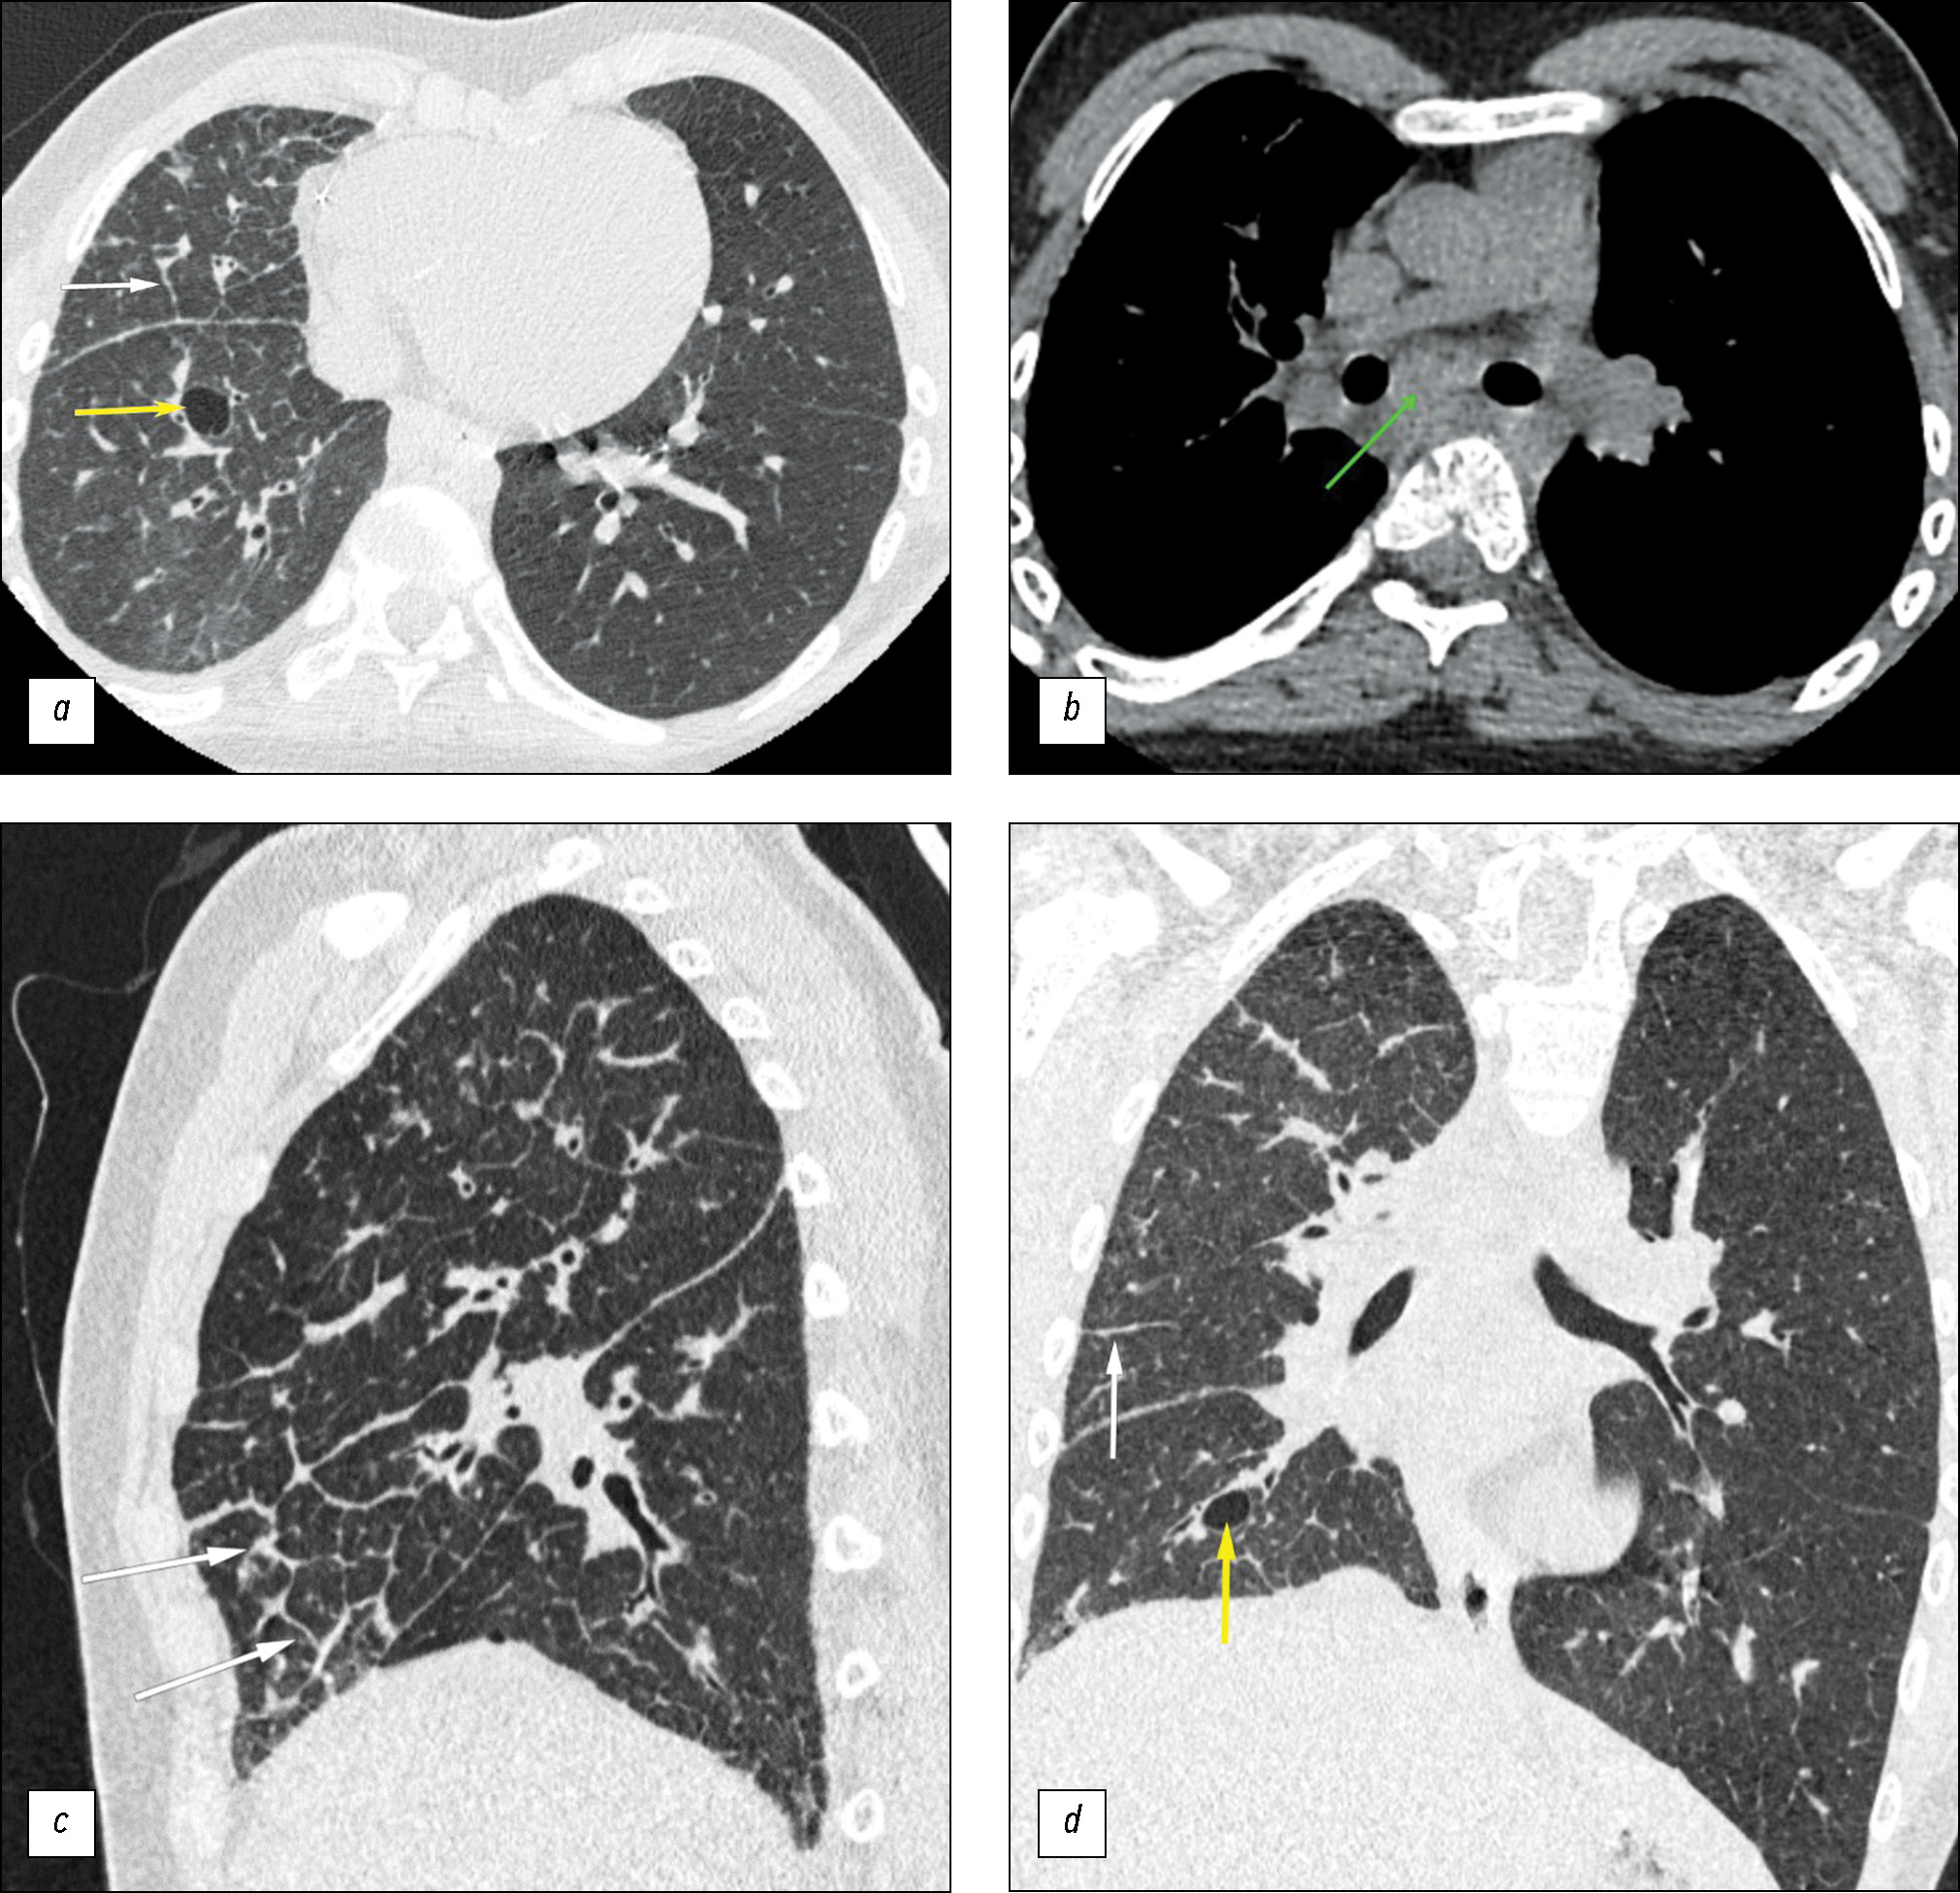

Chest CT without contrast was performed to further diagnose the abnormalities. The scan showed interstitial lesions in the right lung, presenting as thickened intra- and interlobular septa, mainly in the middle and lower parts of the right lung, and thickened bronchial walls. Moreover, in the mediastinum, an irregular soft tissue conglomerate was detected in the right tracheobronchial and subcarinal lymph nodes, with a homogeneous structure and density of +40 HU. The findings indicated intrathoracic lymphadenopathy and interstitial disease of the right lung with evidence of bullous emphysema (Fig. 2).

Fig. 2. Computed tomography of the lungs; (a, b) axial plane; (c) sagittal plane; (d) coronal plane. The volume of the right lung is decreased. White arrows: thickened interlobular interstitium. Yellow arrows: lung cyst. Green arrow: homogeneous soft tissue conglomerate with a density of +40 HU in the mediastinum. Computed tomography in 2023 showed no changes over time.

In 2023, after consultation with an oncologist, the patient was referred for laboratory tests (results within reference limits). As part of watchful waiting, chest, abdominal, and pelvic CT was performed with intravenous contrast. The scan showed persisting decreased volume of the right lung with significant interstitial abnormalities, ground-glass opacity, and cysts in the affected lung. No changes from the previous scan dated 2020 were noted.